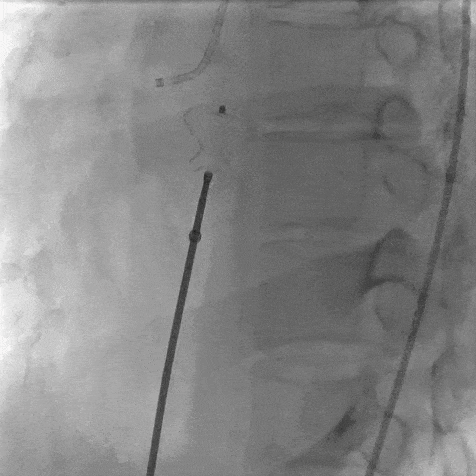

患者局麻后穿刺右股动脉及股静脉,经股动脉送入猪尾导管分别行左心室造影+主动脉根部行根部造影提示主动脉窦瘤破裂(无冠窦-右心房),持续大量左向右分流。明确病变位置后建立股动静脉轨道,经右侧股静脉送入输送鞘并送入先健12/14mm PDA封堵器。再次造影无分流,超声提示窦瘤破裂封堵完好,基本无残余分流,主动脉瓣未受影响。

植入PDA 12/14封堵器后先行冠脉造影评价有无影响冠脉血流